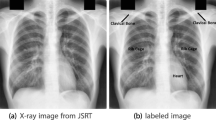

Lung and respiratory ailments are among the leading causes of illness and fatalities. Coronavirus disease (COVID-19), caused by the SARS-CoV-2 virus, has convinced the world that early and affordable detection improves treatment. X-ray imaging systems are inexpensive and widely available. Chest X-ray (CXR) images are inadequate due to the acquiring environment and technician skill. Hence, CXR image contrast enhancement is necessary for a correct diagnosis. Various lung diseases create variable spatial variation in CXR image contrast and brightness; hence, a single contrast enhancement procedure cannot improve it. In the proposed method CXR images are first classified into four categories depending upon their quality defined by their statistical parameters, before applying adaptive gamma correction for contrast enhancement. The performance of the proposed method is compared with existing methods on four datasets for five different types of lung diseases. The performance of the proposed algorithm is evaluated using parameters, such as Root Mean Square Contrast (RMSC) to determine the relation of contrast enhancement between the original and enhanced image, Contrast Improvement Index (CII) to measure the achieved contrast enhancement and Tenengrad which calculates the variation of intensity in the direction of maximum gradient descent. The qualitative and quantitative performance of the proposed method is found better than the existing methods for CXR images for all five lung diseases, which shows the stable performance of the proposed method and improvement in the processed images.

Yadav, V.K., Singhai, J. Adaptive gamma correction for automatic contrast enhancement of Chest-X-ray images affected by various lung diseases. Multimed Tools Appl (2024). https://doi.org/10.1007/s11042-023-18083-x